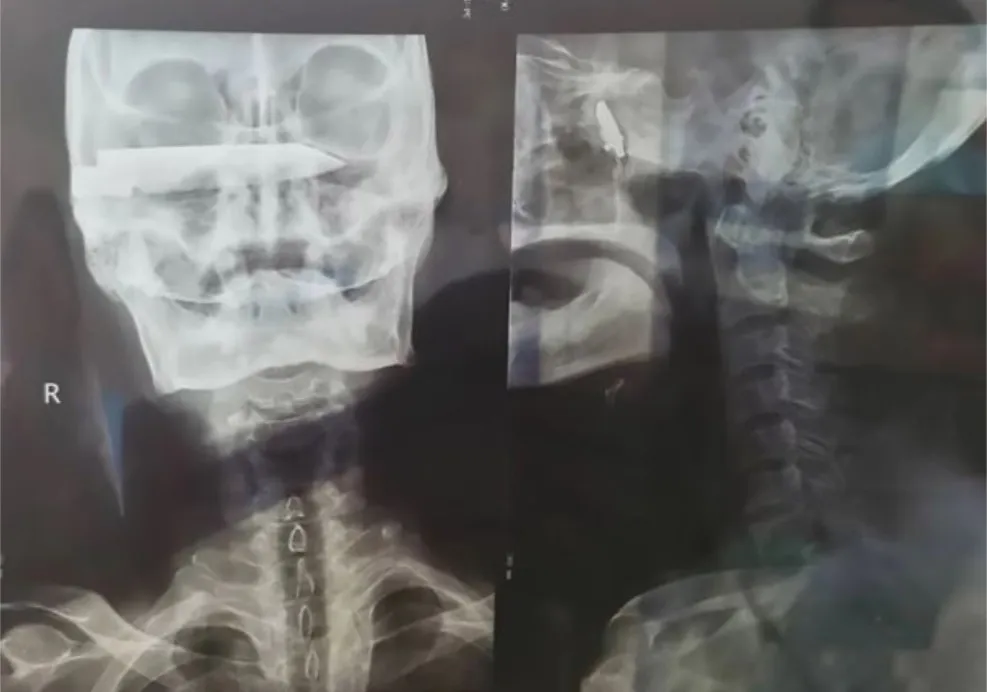

Az 1990-es években megtámadtak egy kínai kecskepásztort, és azóta egy 10 centis késsel a koponyájában mászkált. A 76 éves férfit most műtötték meg, de még az orvosok is elámultak, amikor meglátták a röntgenképét.

A férfinak a csodával határos módon csak 2012-ben okozott panaszt a kés, akkor borzalmas fejfájással fordult orvoshoz. De akkor nem merték megműteni, mert nem találtak megfelelő specialistát.

Idén április 2-án és 8-án megműtötték és sikeres volt a beavatkozás – írta a Daily Star.